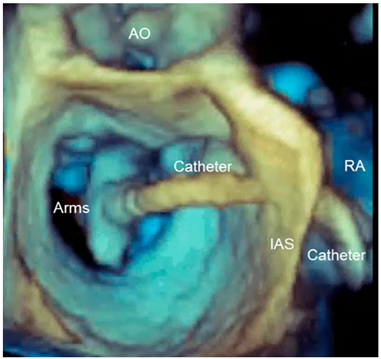

| Panoramic view | 3D TEE has the ability to include in a single panoramic view the mitral clip delivery system (clip, catheter) and the anatomic structures involved in the procedure with an acceptable volume rate. |  |